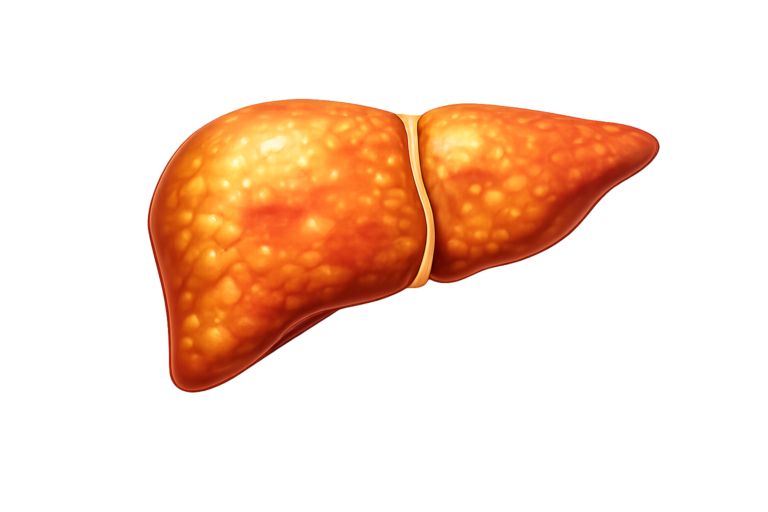

MSLD

Fat accumulation in the liver, i.e. Steatosis

MSLD

Fat accumulation in the liver, i.e. Steatosis